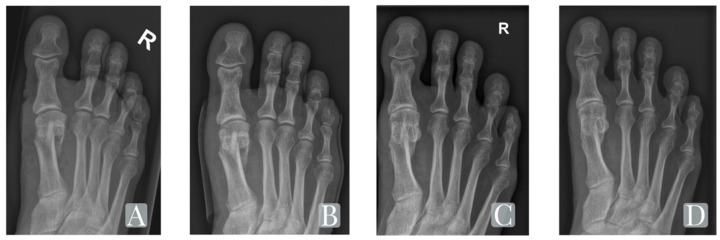

HALLUX VALGUS FOLLOW-UP

Radiographic progression from a bunion correction case demonstrating integration from implantation through 27-month follow-up — the screw progressively becomes indistinguishable from native bone.

Pre-Op

Hallux valgus deformity

Post-Op

Screw implanted

3 Months

Active remodeling

27 Months

Native bone integration

Representative case. Individual patient outcomes vary. Images courtesy SurgeBright. For full clinical data and indications for use, contact your Strategic Surgical representative.